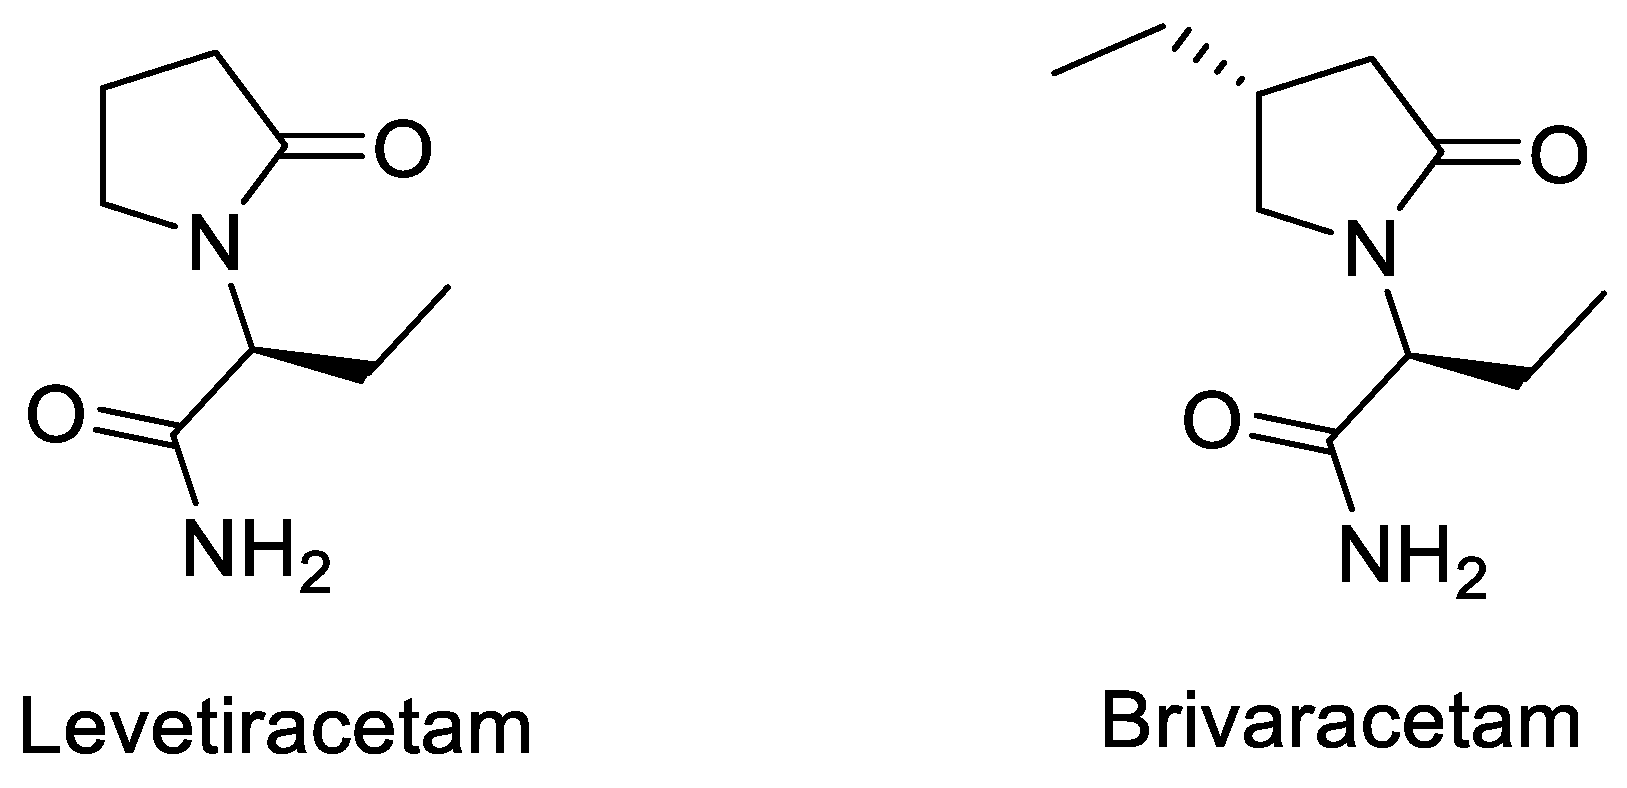

- Lynch, B.A.; Lambeng, N.; Nocka, K.; Kensel-Hammes, P.; Bajjalieh, S.M.; Matagne, A.; Fuks, B. The Synaptic Vesicle Protein Sv2a Is the Binding Site for the Antiepileptic Drug Levetiracetam. Proc. Natl. Acad. Sci. USA 2004, 101, 9861–9866. [Google Scholar] [CrossRef] [PubMed] [Green Version]

- Klitgaard, H.; Verdu, P. Levetiracetam: The First Sv2a Ligand for the Treatment of Epilepsy. Expert Opin. Drug Discov. 2007, 2, 11. [Google Scholar] [CrossRef]

- Gillard, M.; Fuks, B.; Leclercq, K.; Matagne, A. Binding Characteristics of Brivaracetam, a Selective, High Affinity Sv2a Ligand in Rat, Mouse and Human Brain: Relationship to Anti-Convulsant Properties. Eur. J. Pharmacol. 2011, 664, 36–44. [Google Scholar] [CrossRef]